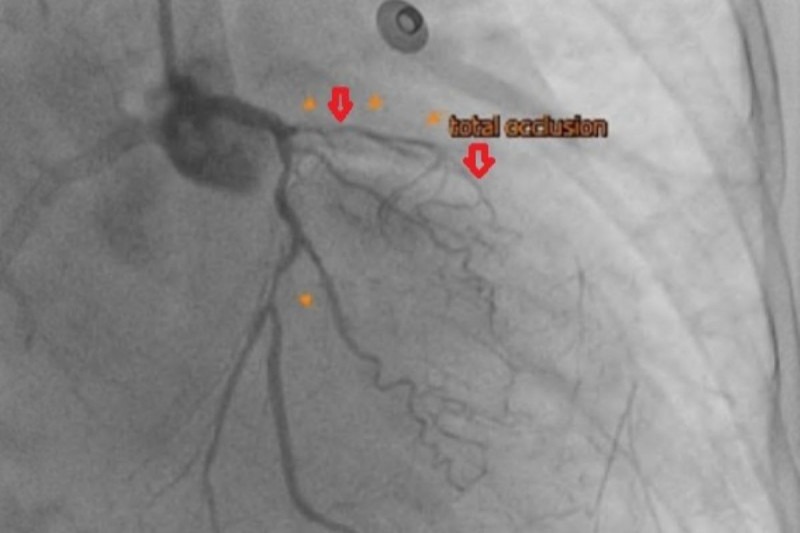

〔記者翁聿煌/新北報導〕63歲陳女士3個月前出現呼吸越來越喘、胸悶不適等症狀,到院心導管檢查發現其左前降支合併完全阻塞左迴旋枝狹窄,診斷為缺血性心肌病變,即冠狀動脈阻塞導致的慢性心臟衰竭,醫師採取達文西微創冠狀動脈繞道手術,以左內乳動脈為繞道血管,重新供應左前降支的血流,後續再由心臟血管科醫師進行心導管疏通左迴旋枝的狹窄,術後病患左心室收縮功能明顯進步。

楊凱文說,冠狀動脈疾病在治療選擇上有心導管支架置放及外科手術,前者適用於單一血管狹窄且情況不嚴重或病人手術風險過高;後者則有傳統開胸及達文西微創手術兩種,適用於多條血管嚴重狹窄甚至阻塞的情形,有時則可以採取所謂複合冠脈血流重建的方式,顧名思義是一種結合心臟外科的「微創冠狀動脈繞道手術 (MIDCAB)」與心臟內科的「經皮冠狀動脈介入治療 (PCI)」的治療方式,旨在融合兩者優點,為複雜的冠心病患者提供更佳的血流重建。